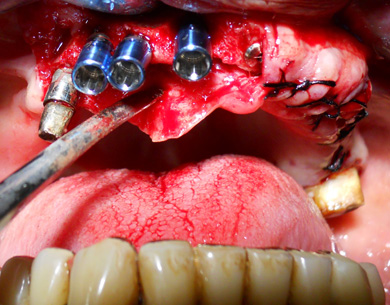

Su richiesta del paziente, si decide di eseguire una protesi fissa su impianti con chirurgia computer-guidata. Dopo Tac arcata superiore e scansione 3D del progetto protesico, si esegue l'accoppiamento virtuale di entrambi. Su questo si progettano profondità e inclinazione degli impianti che vengono inseriti virtualmente. Si realizza poi una dima chirurgica e una protesi. Quindi in maniera assolutamente non invasiva vengono inseriti flapless 6 impianti e successivamente, dopo adattamento, avvitata la protesi toronto. (intervento e foto eseguiti da me in 2h e 30 min)